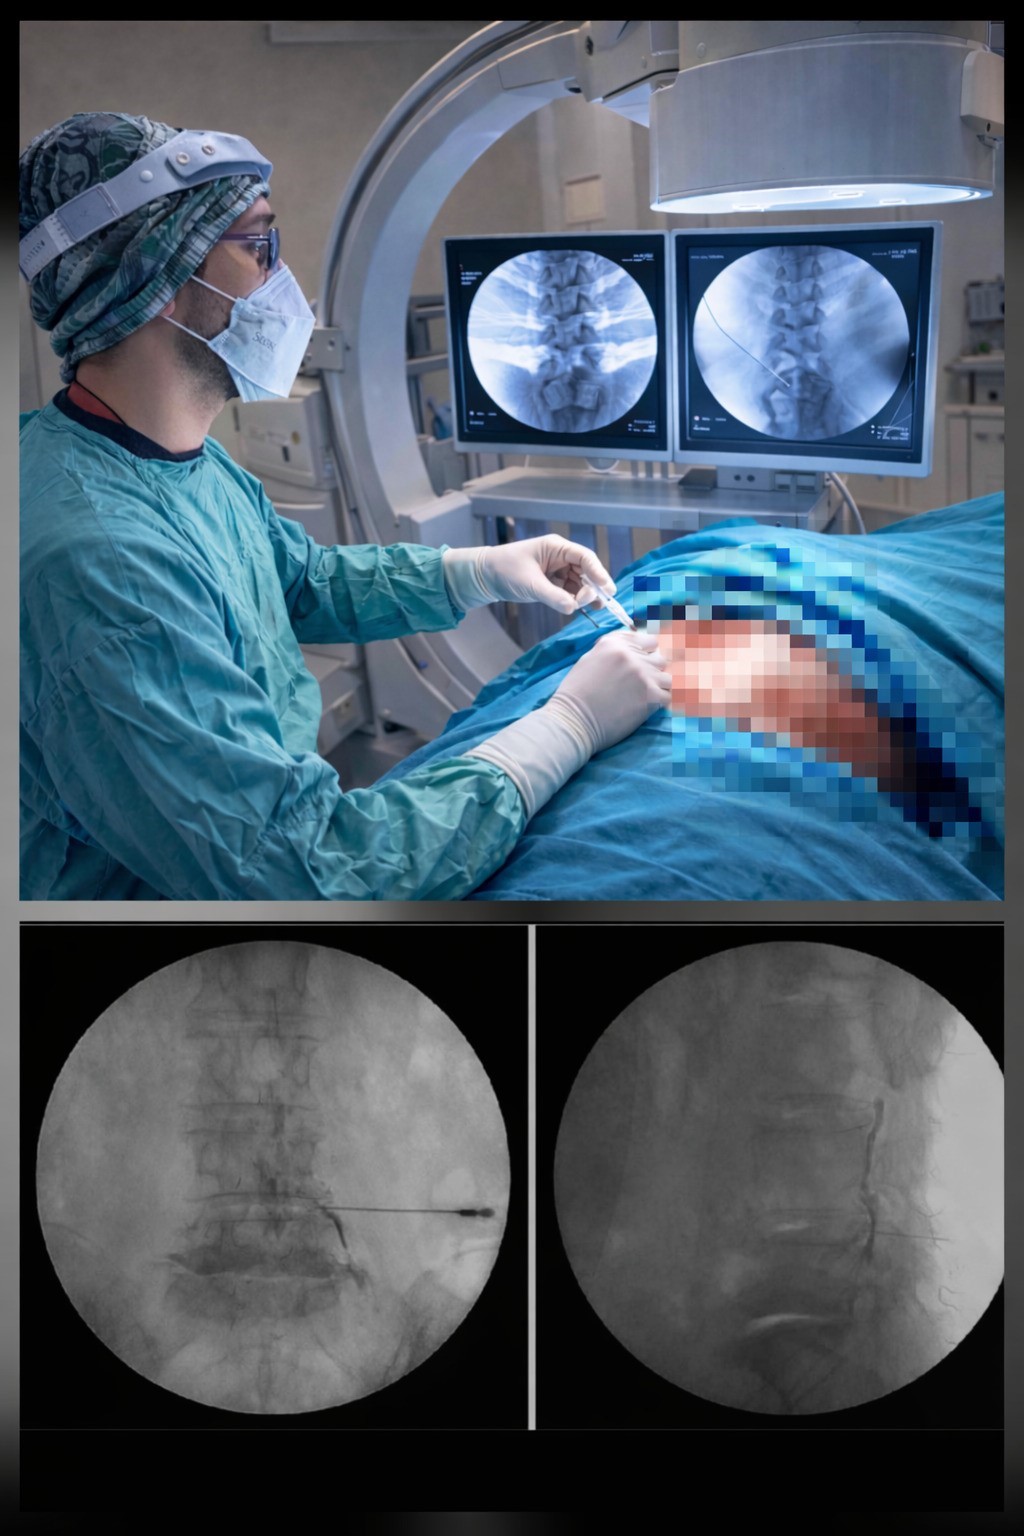

Ezine Devlet Hastanesi, bel fıtığı tedavisinde önemli bir yeniliğe imza attı. Ortopedi ve Travmatoloji Uzmanı Op. Dr. Ersen Türkmen tarafından hastanede ilk kez Transforaminal Epidural Steroid Enjeksiyonu (TFESI) yöntemi başarıyla uygulanmaya başlandı. Nokta atışı tedavisi olarak da bilinen bu modern yöntem, ameliyatsız çözüm sunarak hasta konforunu ve yaşam kalitesini belirgin şekilde artırıyor. Bel fıtığı, günlük yaşamı ciddi şekilde etkileyen, şiddetli bel ve bacak ağrılarıyla seyreden önemli bir sağlık sorunuyken uygulanan bu yeni yöntem sayesinde, hastalar artık cerrahiye gerek kalmadan etkili bir tedavi seçeneğine ulaşabiliyor. TFESI, fıtığın sinir köküne yaptığı baskının neden olduğu ağrı ve iltihabi süreci hedef alarak doğrudan problemli bölgeye tedavi uygulanmasını sağlıyor. Ameliyathane ortamında, görüntüleme eşliğinde yapılan bu işlem: küçük girişimsel, genel anestezi gerektirmez, süresi kısa, yatış gerektirmeyen bir işlem. Bu sayede hastalar günlük yaşamlarına çok kısa sürede dönerek iş gücü kaybı ve uzun istirahat süreçleri büyük ölçüde ortadan kalkıyor. Bu modern uygulama sonrası hastalarda: ağrı seviyesinde belirgin azalma, yürüme mesafesinde artış, uyku kalitesinde düzelme, günlük aktivitelerde rahatlama, psikolojik iyilik hâlinde artış gibi yaşam kalitesini doğrudan etkileyen olumlu sonuçlar görülüyor.